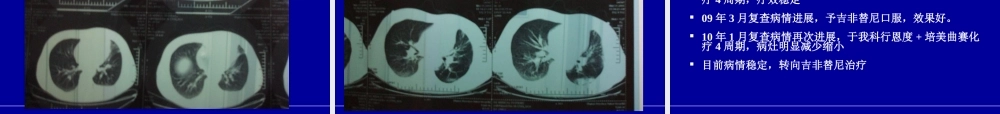

病例分享山西省肿瘤医院郭沁香病例1王XX,男性,61岁,吸烟40年08年3月出现咳嗽,咳痰,气短08年4月第一次入院,确诊为左肺低分化腺癌,锁骨上淋巴结转移,骨转移,Ⅳ期晚期非小细胞肺癌一线治疗策略晚期NSCLC非鳞癌鳞癌EGFR突变阳性:TKI靶向治疗或三代化疗药联合铂类的化疗EGFR突变阴性:三代化疗药联合铂类的化疗EGFR突变未知:三代化疗药联合铂类的化疗三代化疗药联合铂类的化疗SD、PR,CR——可选择维持治疗进展——二线治疗病例1王XX,男性,61岁,吸烟40年08年3月出现咳嗽,咳痰,气短08年4月第一次入院,确诊为左肺低分化腺癌,锁骨上淋巴结转移,骨转移,Ⅳ期GP方案化疗4周期,疗效近CR化疗前(08-4)化疗两周期(08-6)化疗四周期(08-8)延缓进展时间确诊CR/PR/SDPDPD维持治疗新模式确诊CR/PR/SD一线治疗含铂两药化疗(4–6周期)‘’观察并等待PD二线或后续治疗PD维持治疗:NSCLC新的治疗模式维持治疗的模式继续应用一线有效的两药方案直到疾病进展一线化疗有效的药物单药维持二线化疗药的提前应用靶向药物维持治疗研究结论继续一线含铂两药方案化疗为阴性结果第三代化疗药单药作为维持治疗中,紫杉醇、长春瑞滨为阴性结果,健择是阳性结果,分层分析发现:对于KPS状况好者,健择维持治疗后生存延长,状况差者,和对照无差异。多西他赛维持治疗明显延长了PFS,OS有优势,但无统计学差异,同时有较高的缓解率与疾病控制率。培美曲塞(JMEN)的维持治疗只有非鳞癌患者明显获益,OS增加到15.5月,而非所有患者获益。吉非替尼(WJTOG0203)和厄洛替尼(SATURN)可作为维持治疗的药物,尤其对腺癌和EGFR突变者疗效更好。病例1王XX,男性,61岁,吸烟40年08年3月出现咳嗽,咳痰,气短08年4月第一次入院,确诊为左肺低分化腺癌,锁骨上淋巴结转移,骨转移,Ⅳ期GP方案化疗4周期,疗效近CR08年8月G单药维持2周期病灶增大晚期非小细胞肺癌二线治疗化疗化疗多烯紫杉醇培美曲塞EGFR-TKI靶向治疗吉非替尼厄洛替尼最佳支持治疗二线治疗的选择新药/方案的临床研究内皮抑素作用机理Endostatin能阻止生长因子与受体结合,干扰其信号传导通路[1]。Endostatin能抑制金属蛋白酶活性,阻断其降解细胞外基质[2]。Endostatin能诱导内皮细胞停滞在G1期,阻止内皮细胞分裂[3]。Endostatin能诱导内皮细胞凋亡,发挥抗血管生成作用[4]。Endostatin能阻止内皮细胞的粘附移行,阻断血管生成[5]。1.KimYM,etal..JBC,...